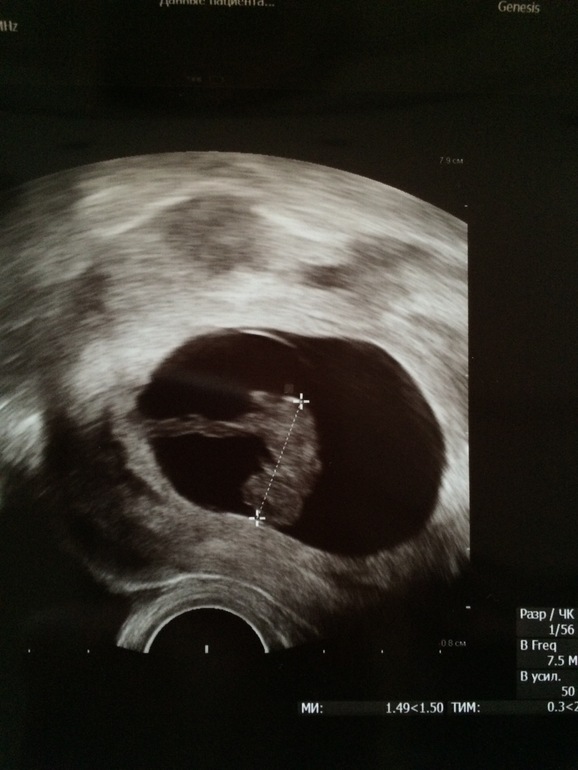

Очередное узи и пол малыша

НЕ ПЕРВЫЙ малышСегодня была на очередном узи - малышок уже совсем малышок, а не огурчик.